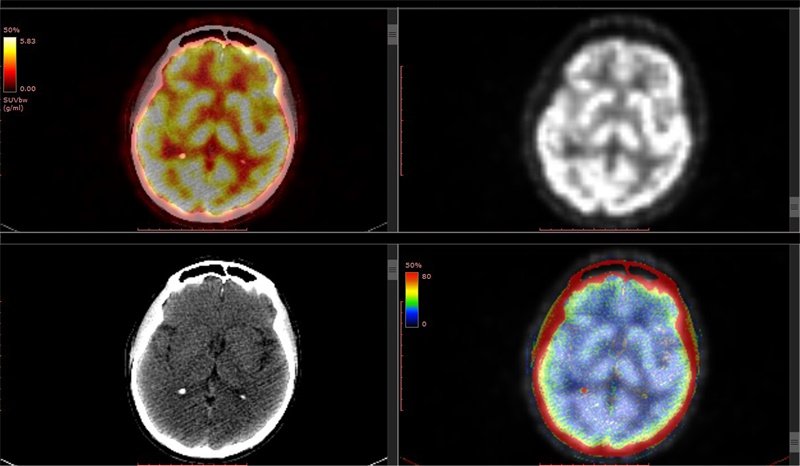

低血糖作为一种常见的健康问题,其对大脑构成的威胁尤其不容...